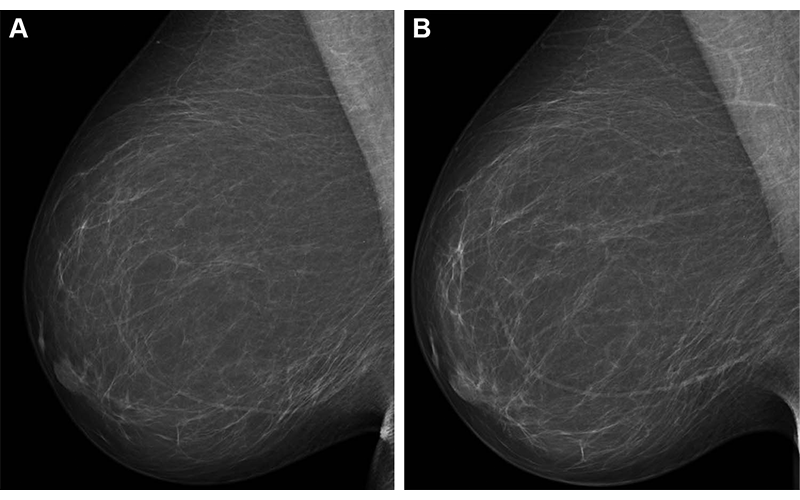

Full-field digital mammograms (right mediolateral oblique view) in a 59-year-old woman show (A) the screening mammogram obtained during the study period and (B) the screening mammogram obtained in the subsequent screening round. The first screening mammogram (A) had a very low combined risk score (lowest 0.1%) as determined by the combination model with texture risk and the examination score. The woman was not recalled and did not receive a breast cancer diagnosis throughout the 5-year follow-up.